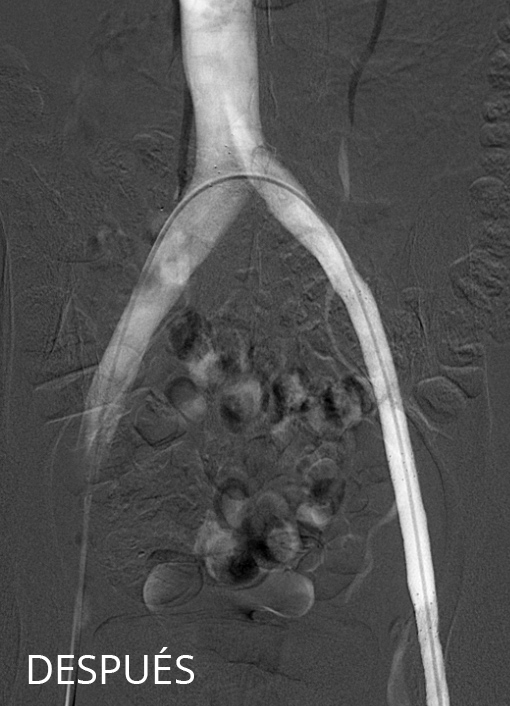

En el caso de la patología venosa pélvica, el tratamiento consiste en embolizar (ocluir) las venas que presentan reflujo y pueden desarrollar varices. El tratamiento de embolización puede hacerse en el mismo momento que la prueba diagnóstica de flebografía pélvica.

El acceso se hace, normalmente desde la vena basílica y, siguiendo nuestro protocolo, en primer lugar canalizamos las venas renal e ilíaca izquierdas para descartar posibles síndromes compresivos. Posteriormente, estudiamos ambas venas gonadales para valorar la morfología de las mismas y la posible existencia de varices pélvicas, en cuyo caso se emboliza el eje gonadal completo hasta 3-5 cm aproximadamente por debajo de la vena renal. Finalmente, se canalizan las venas ilíacas internas para visualizar posibles fugas o reflujos hacia la zona genital y los miembros inferiores, las cuales son embolizadas también en caso de confirmarse. Los 4 ejes (gonadales e ilíacos internos) están intercomunicados entre sí por lo que es muy importante que se exploren todos y se traten aquellos que tengan reflujo.

La técnica habitual de embolización en nuestro equipo es la técnica mixta o en sándwich utilizando coils y microespuma. Los coils empleados son unos dispositivos mécanicos que, unidos a pequeñas inyecciones de microespuma, permiten la completa oclusión de la vena. Es importante embolizar el eje completo para evitar posibles repermeabilizaciones. El número de coils se determinará en cada caso en función de las necesidades.